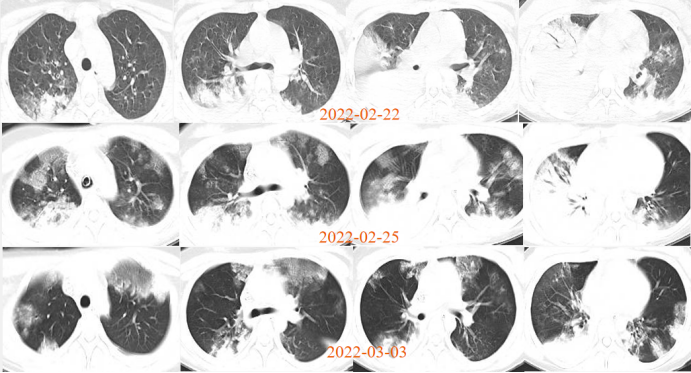

临床案例:患者女性,15岁,诊断为重症支原体肺炎、ARDS,低氧高碳酸血症,气管插管接呼吸机辅助通气,采用肺保护性通气策略及俯卧位通气后效果不佳。2022年2月22日启动VV-ECMO治疗,2月25日转为清醒ECMO,最终患者病情好转出院。

图片

3  清醒EMO前后患者胸部CT对比